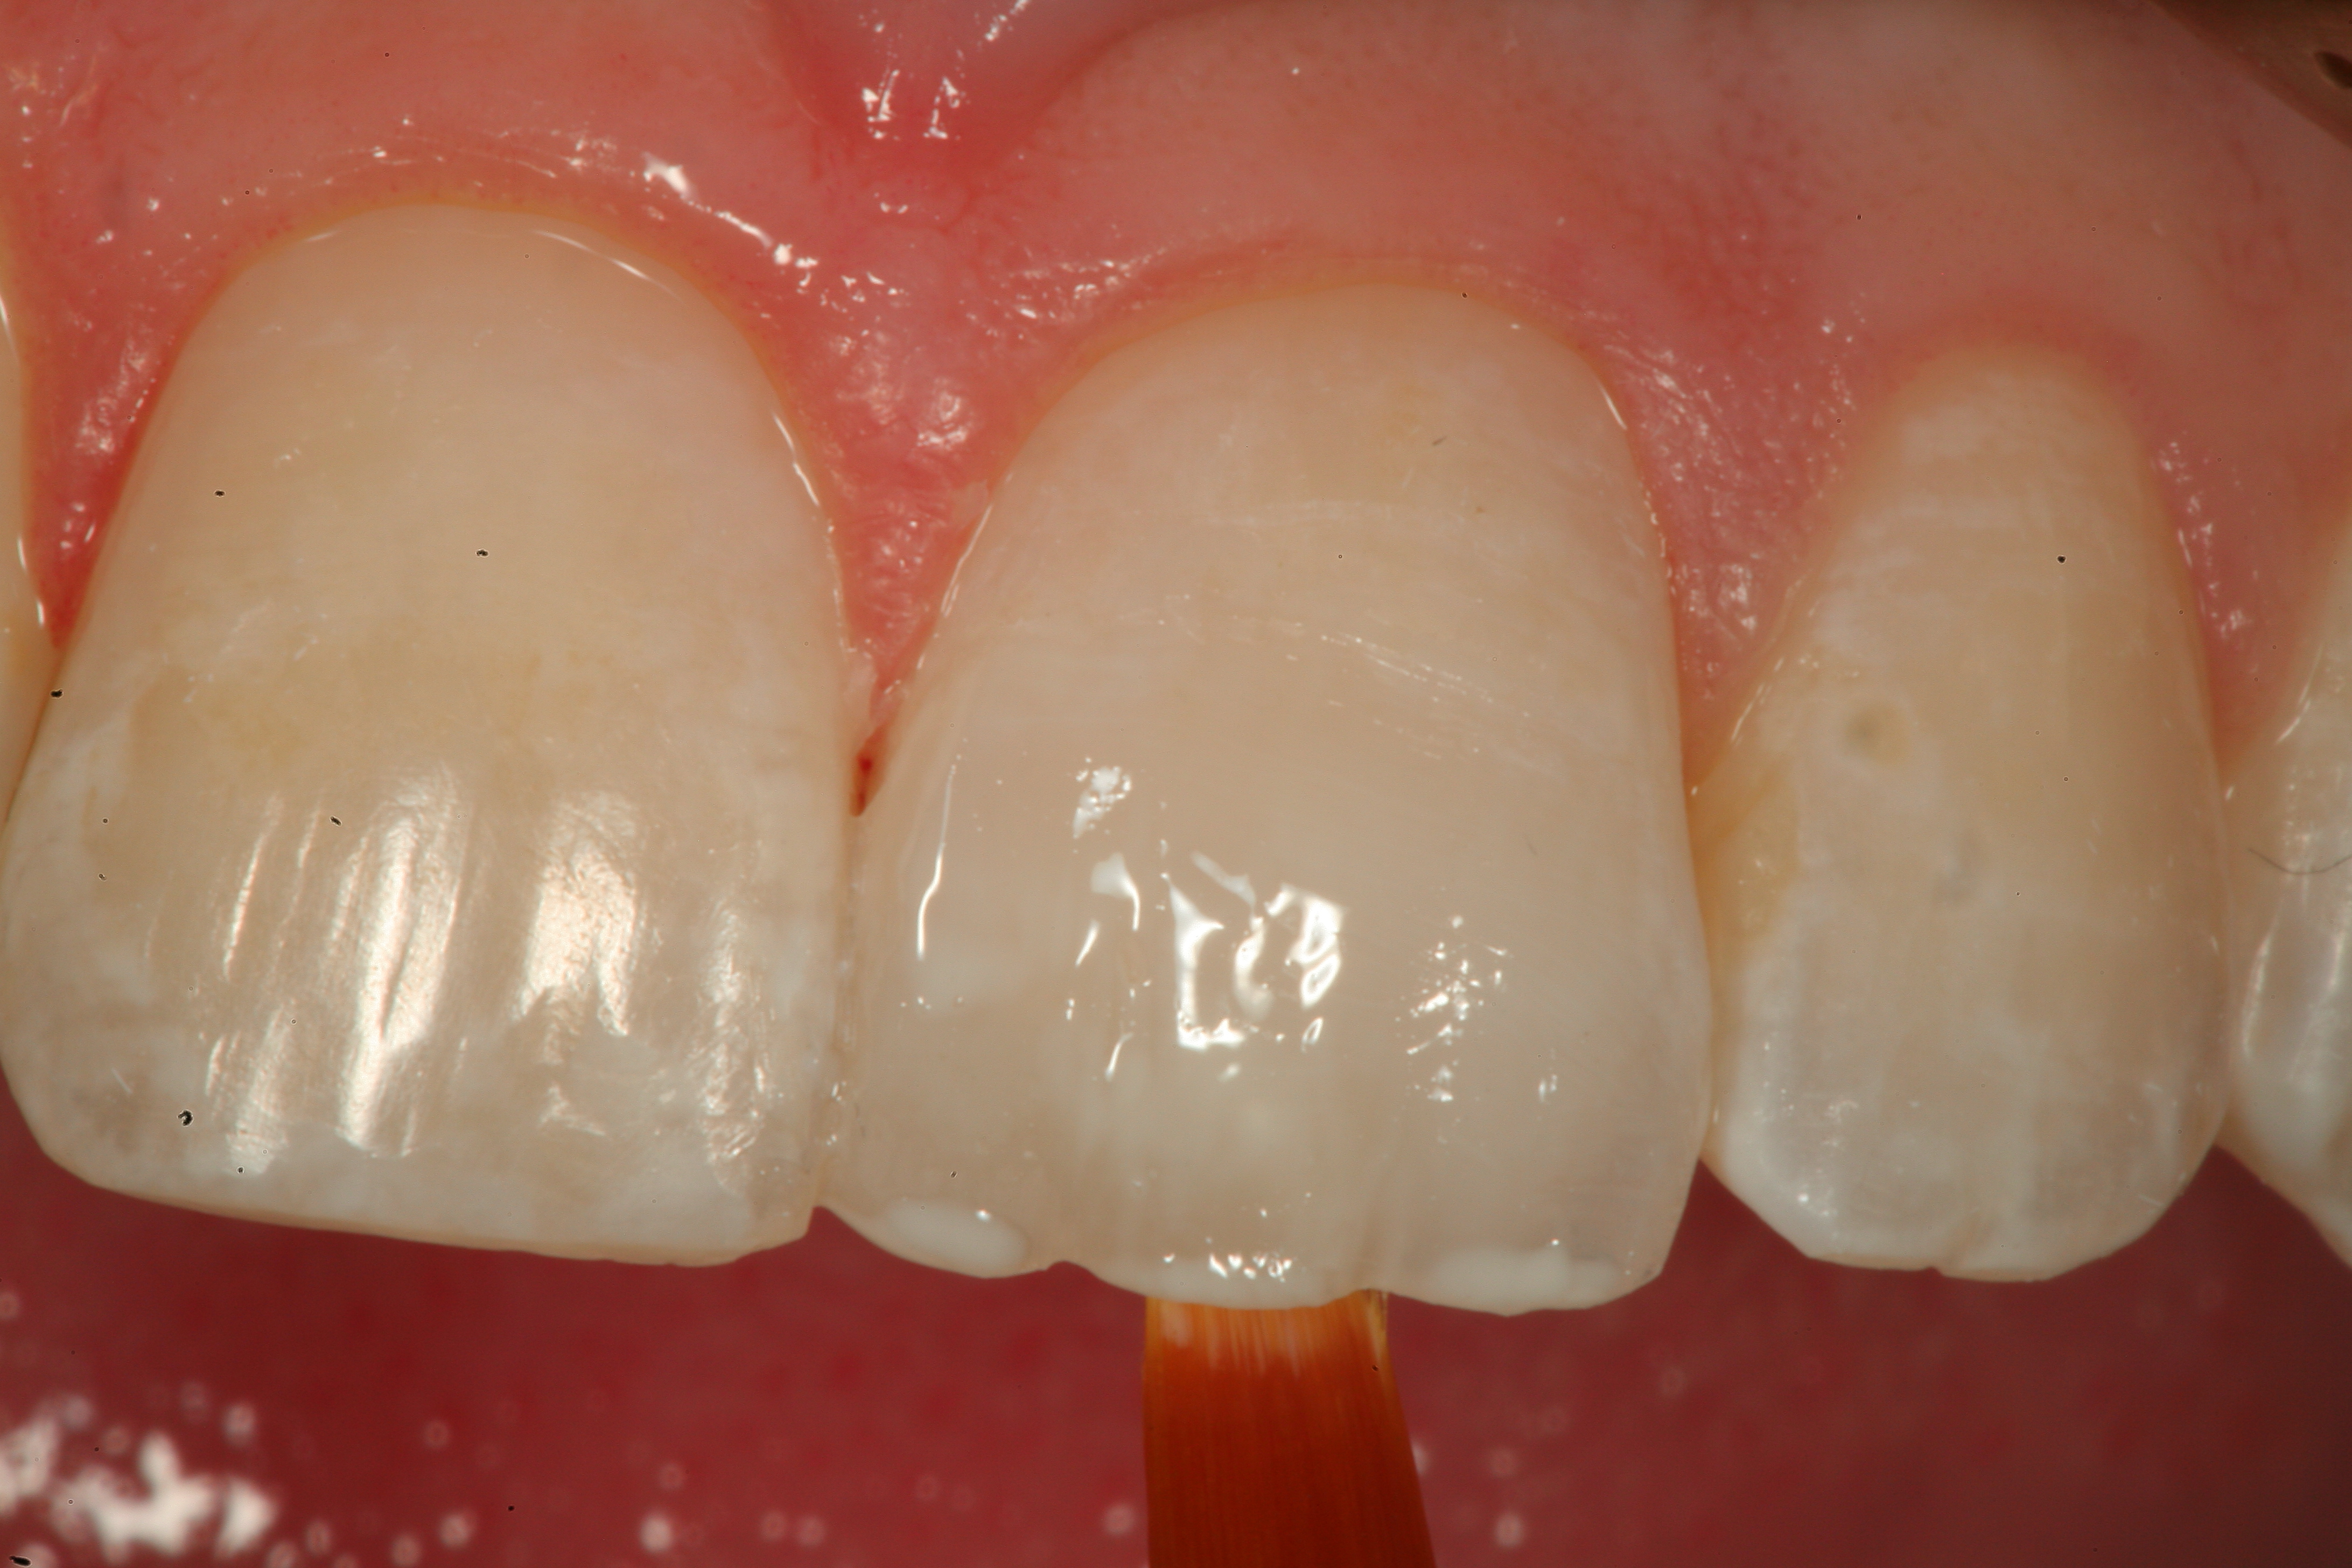

Fig 12. A Class IV mesial incisal fracture is shown from the facial aspect on tooth No. 9.

Figure 12

Fig 13. After placement of a bevel on the facial surface 2 to 3 mm from the position of the fracture, the enamel is etched and rinsed, and an adhesive resin is scrubbed into the prepared surface.

Figure 13